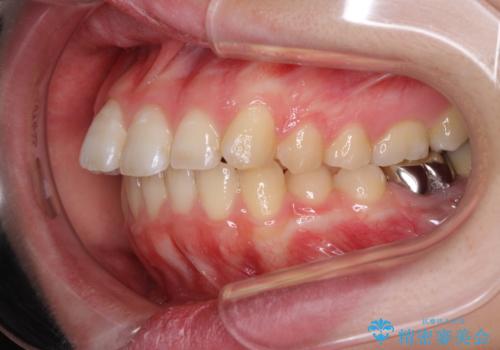

- 口の閉じにくさと割れてしまった奥歯を気にして来院された患者様です。

IPR(歯と歯の間を削る)と歯列全体の後方移動によって口元が引っ込むように設計し、インビザラインにより治療を行うこととしました。

割れてしまった奥歯は抜歯し、矯正治療中の良いタイミングでインプラントを埋入することとしました。

インプラントは、治療期間を短くすることが可能な、ストローマン社のSLActiveを使用することとしました。

上下正中がずれていたため、抜歯による矯正治療も検討しましたが、口元がそれほど突出していなかったため、非抜歯にて矯正することになりました。

その結果正中のズレは残りましたが、口を閉じたときの感覚や奥歯の咬み合わせには全く問題なく、患者様には大変満足していただきました。